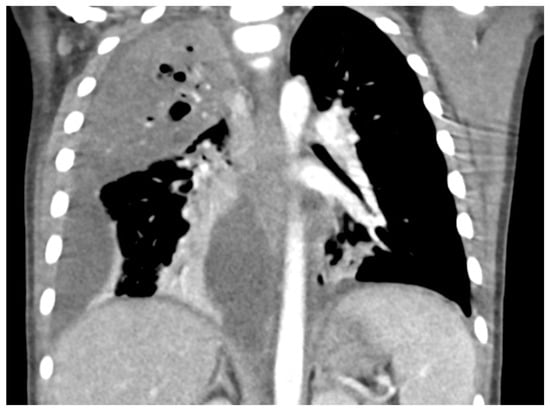

- Carrard, J.; Bacher, S.; Rochat-Guignard, I.; Knebel, J.-F.; Alamo, L.; Meuwly, J.-Y.; Tenisch, E. Necrotizing pneumonia in children: Chest computed tomography vs. lung ultrasound. Front. Pediatr. 2022, 10, 898402. [Google Scholar] [CrossRef]

- Lai, S.-H.; Wong, K.-S.; Liao, S.-L. Value of lung ultrasonography in the diagnosis and outcome prediction of pediatric community-acquired pneumonia with necrotizing change. PLoS ONE 2015, 10, e0130082. [Google Scholar] [CrossRef]